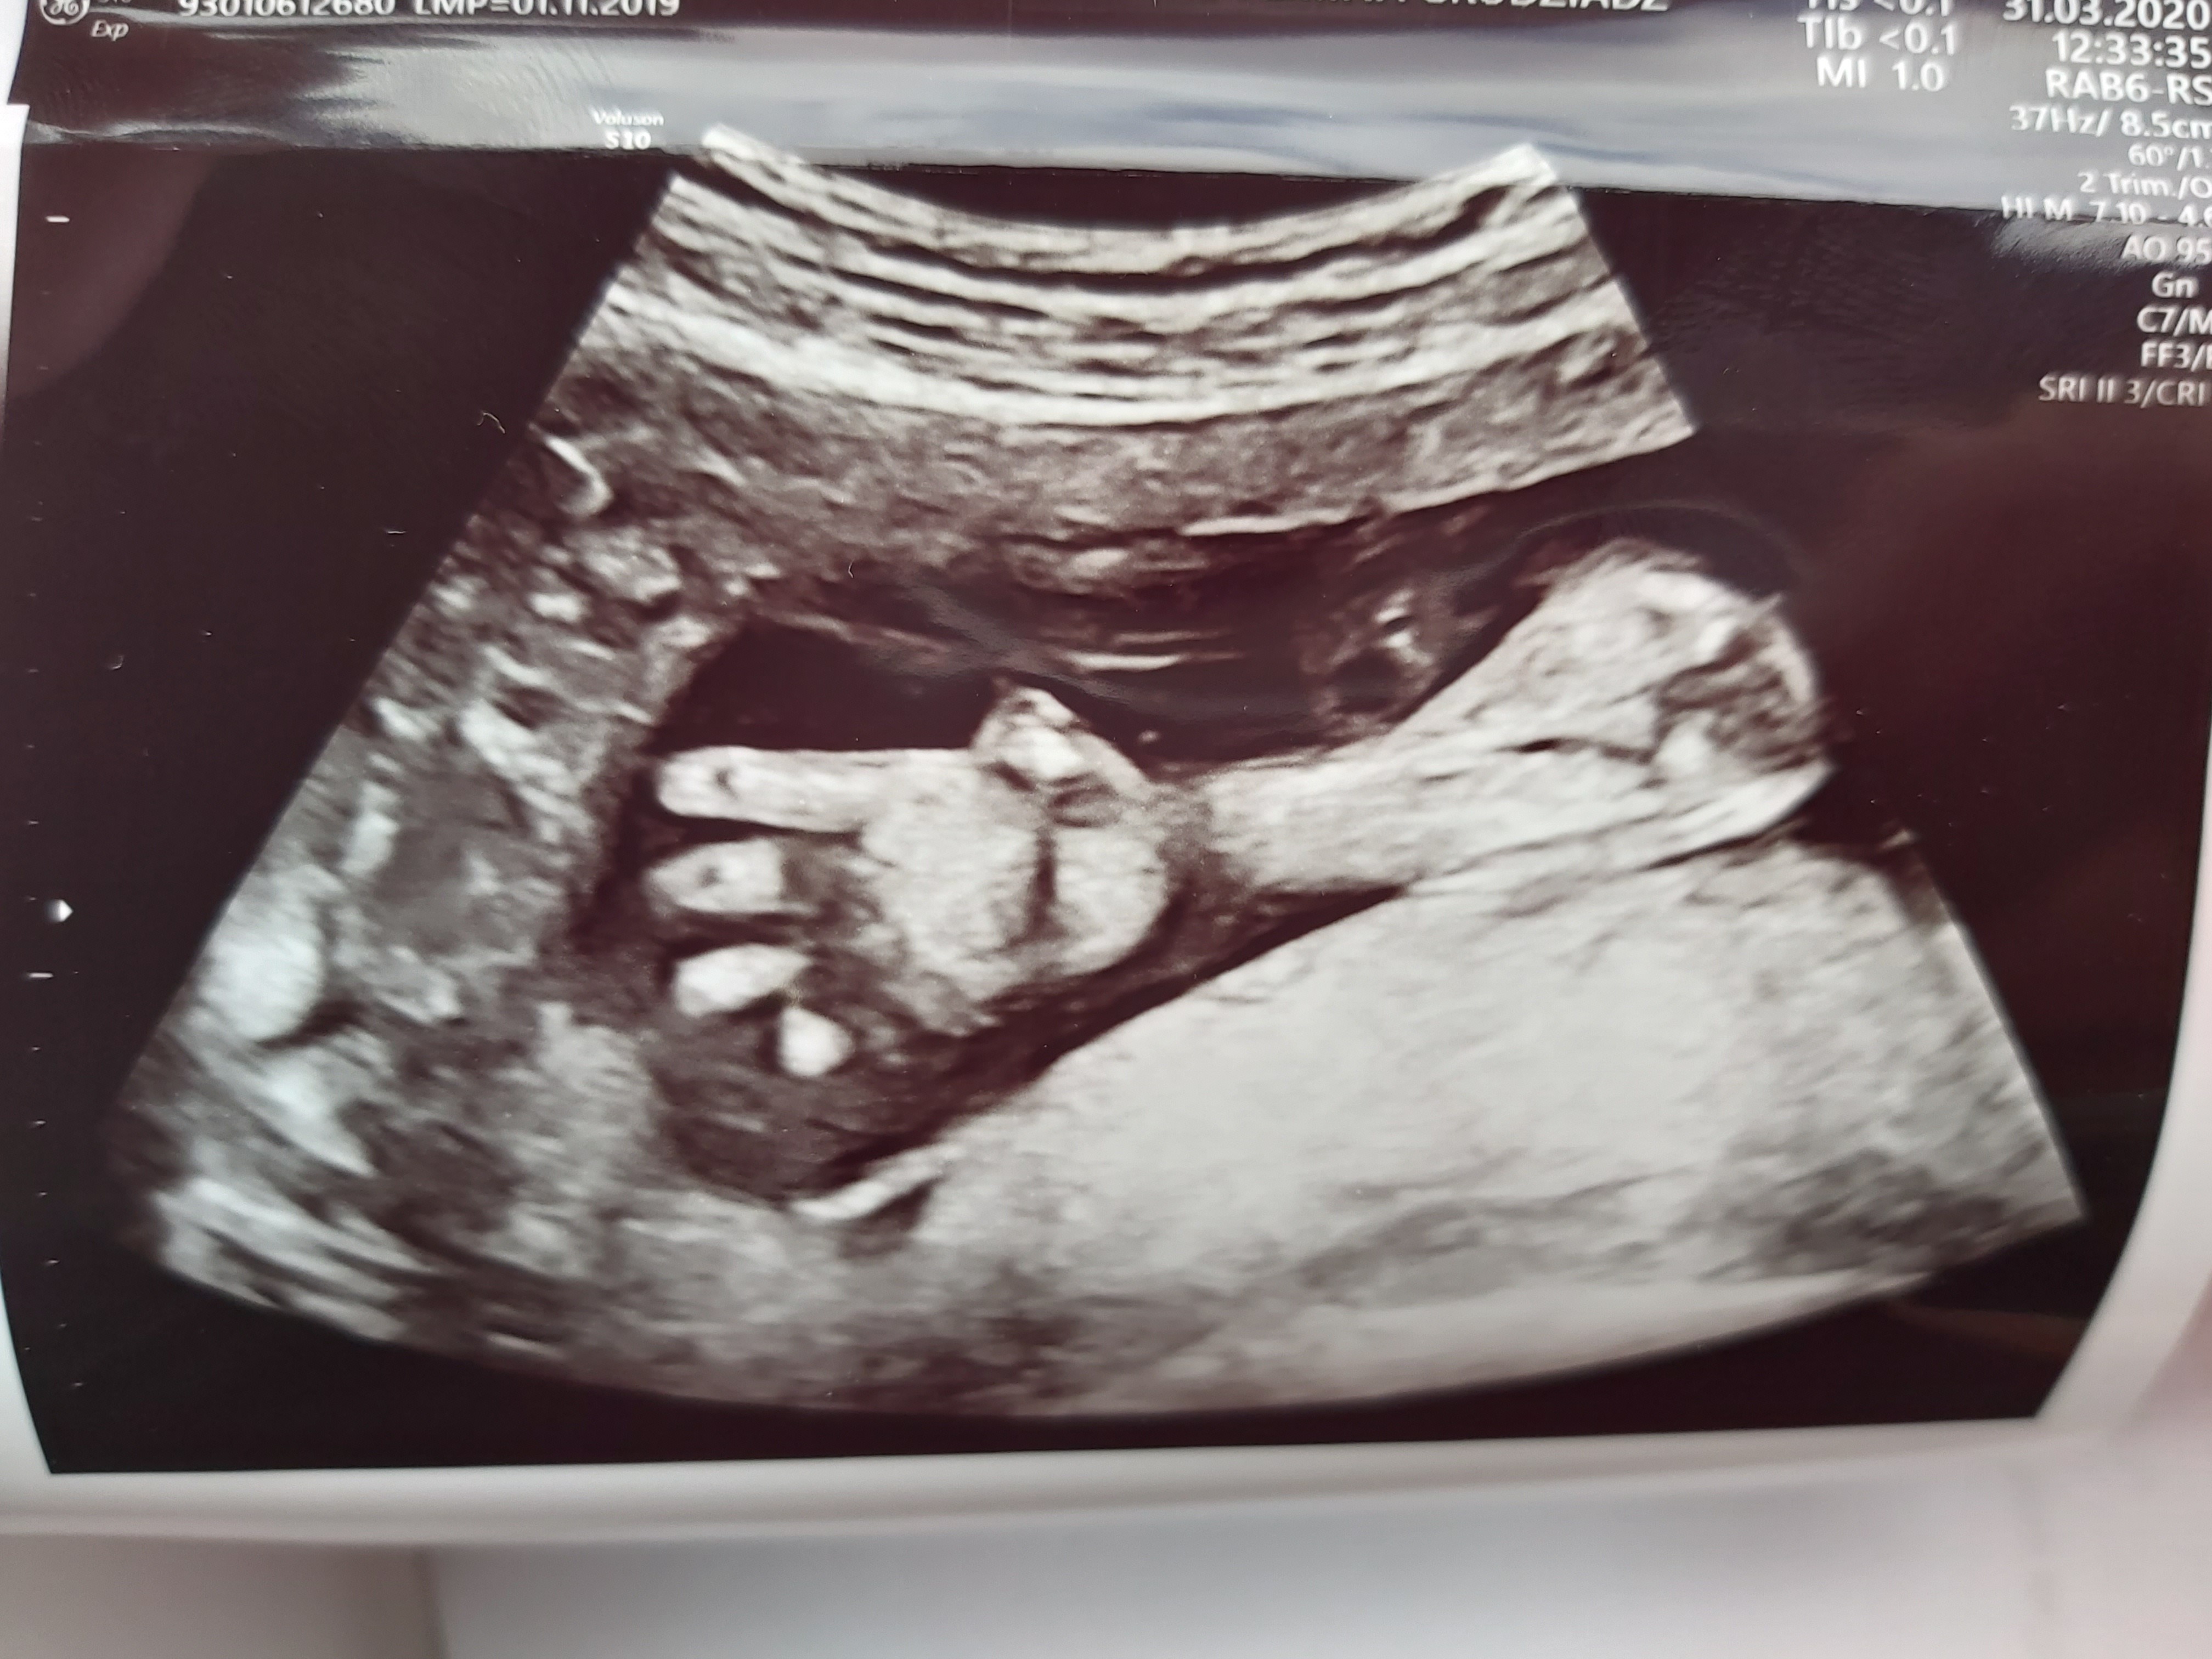

Szczęśliwa...:)